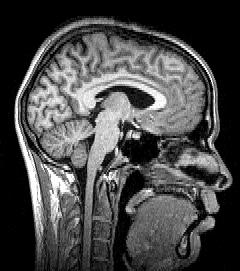

Median plane sagittal tomography of the head by magnetic resonance imaging